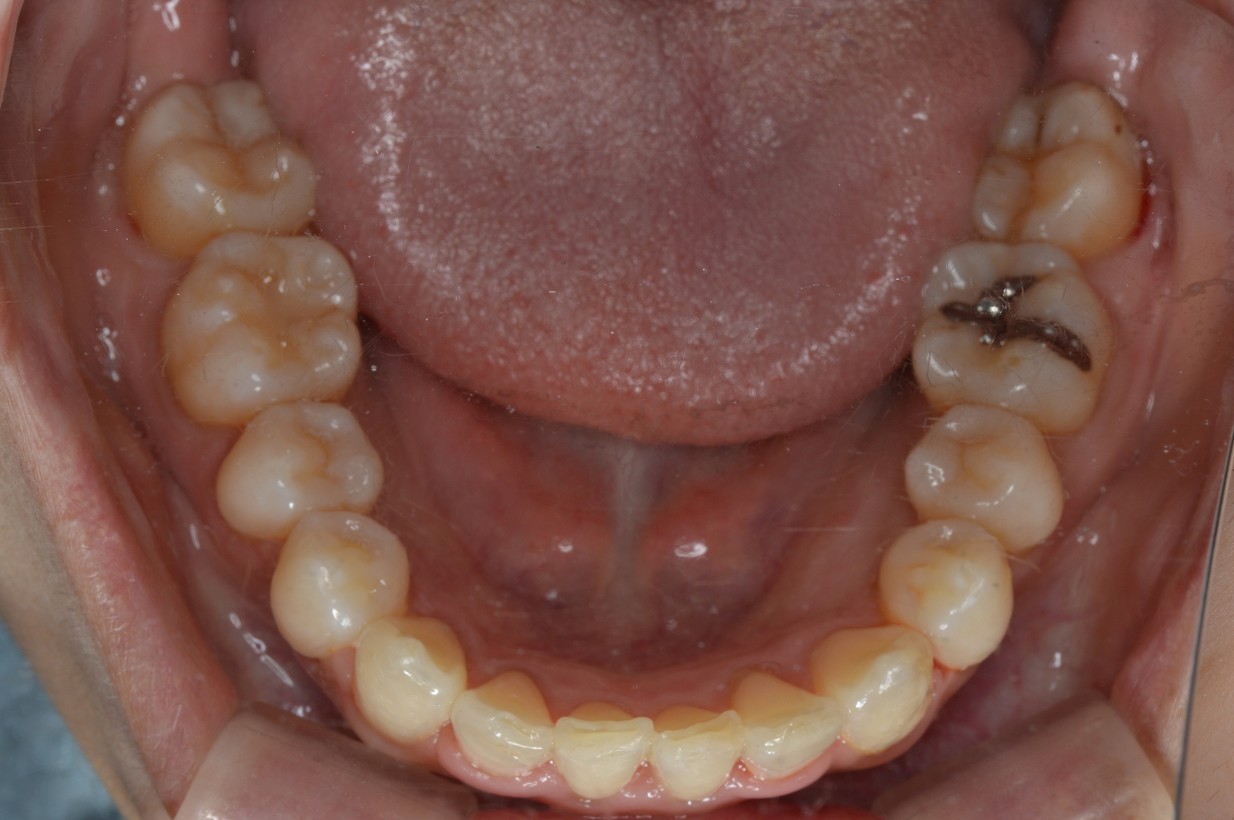

症例2

| 項目 | 詳細 |

|---|---|

| 患者様データ | 30代 女性 |

| 来院時の主訴 | 「右上の、内側に生えている歯が邪魔。」 |

| 矯正法 | 上の歯2本、下の歯2本、親知らず3本を抜歯しての矯正 |

| 通院期間 | 3年6ヶ月 |

| 治療費 | 総額:1,230,000円(税抜) 【内訳】 精密検査50,000円、メタルワイヤー矯正800,000円、月に1度の調整料5,000円、後戻り防止のリテーナー35,000円×2 |

| リスクと副作用 |

①歯を動かす事による痛みがあります。また、装置に慣れるまでは、口内炎ができやすいです。 ②歯肉が退縮するリスクがあります。装置が全ての歯に付くので、ハミガキが難しくなります。 ③長期的なメインテナンスが必要 |

| ここがこだわりのポイント!☝ | こちらの患者様は上の歯が1本内側に生えていましたが、奥歯の噛み合わせの方が問題でした。ハサミ状咬合といい、奥歯が極端に外側に向いており、下の歯と噛み合っていない状態でした。ハサミ状咬合は長期的にみると、前歯に大きな負担がかかったり、磨きにくい事による虫歯や歯周病になりやすいなどのリスクがあります。治療期間はかかりましたが、見た目の良さだけでなく、機能的にも改善しました。 |